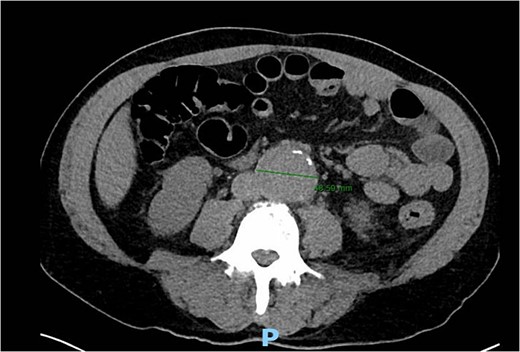

A 56-year-old male with no reported past medical history and a 70 pack year smoking history presented with a chief complaint of lower abdominal pain and body aches. On presentation, the patients white blood cell count (WBC) was 39.6 and procalcitonin was 43.4. Blood cultures were drawn and demonstrated P. mirabilis bacteremia. Computed tomography (CT) abdomen/pelvis was performed as well as ultrasound (US) of scrotum demonstrating a complex fluid collection within scrotal sac that was determined to be a scrotal wall abscess. The patient was started on a course of Unasyn and Urology promptly took him to the operating room (OR) for incision and drainage. Vascular surgery was consulted due to an incidental finding of an abdominal aortic aneurysm on CT measuring 4.7 × 4.6 cm (Figs 1 and 2). The patient was evaluated by the vascular surgery team following his urological procedure and denied any history of abdominal pain or back pain. Physical exam was largely unremarkable however the patient’s bilateral toes were noted to have blue discoloration with motor and sensation intact. Outpatient follow up with routine US scans for the AAA was recommended. Ankle brachial index (ABI) as well as an echocardiography was ordered to further work up the patient’s dusky toes. On Day 2 of hospitalization, ABIs returned showing severe peripheral vascular disease (PVD) and the echocardiography ruled out endocarditis. At this time an angiogram was planned to further the patient’s PVD workup however this was deferred as the patient remained septic with a WBC of 30. Over the course of the next few days the patient refused antibiotics and remained septic with a WBC in the 20s. At this time his toes quickly deteriorated from dusky to dry gangrene. On Day 8 of hospitalization the patient remained septic and was now complaining of new onset mid-abdominal pain. Emergent CT showed AAA was now 7.7 × 7.8 cm with periaortic fat stranding concerning for impending rupture (Figs 3 and 4). The patient was taken emergently to the OR for open repair. Upon visualization, the abdominal aortic aneurysm was clearly infected with signs of impending rupture on the left lateral wall and purulent material including infected thrombus. Tissue was cultured however showed no growth, likely due to the fact that the patient had been on antibiotic therapy for a week at this time. Reconstruction with an aorto-biiliac bypass using rifampin-soaked dacron graft was performed. A piece of omentum was mobilized over the graft and the retroperitoneum was closed over it. The abdomen was left open for a return to the OR for a second look which showed no concerns for bowel ischemia, worsening infection or bleeding. On post-op Day 5 the patient was extubated, off pressor support, and transferred to the floor. The patient’s postoperative course was unremarkable except for bilateral toes demarcating to dry gangrene.

Axial CT angiography of the abdomen and pelvis demonstrating 7.7 cm AAA with fat stranding.